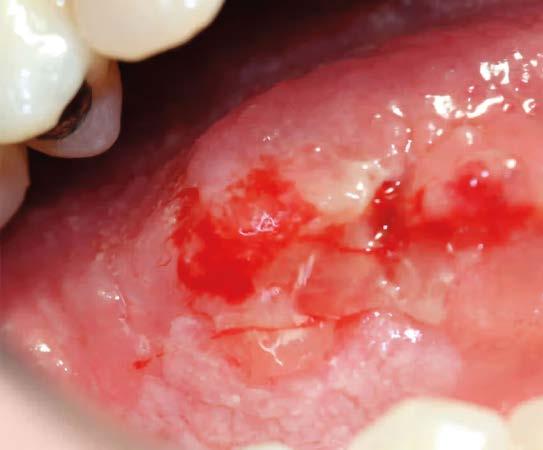

Juan Pancracio, un paciente de 71 años, llega a la consulta del urólogo con una lesión ulcerativa poco profunda de 1 cm en el surco balanoprepucial, no dolorosa ni supurativa, que ha aparecido hace un mes. El médico le prescribe antibióticos y cremas cicatrizantes, y le indica que vuelva en dos semanas para el seguimiento.

Don Juan se pierde y vuelve cinco meses después, esta vez acompañado por su esposa, doña Rosa, quien lo ha obligado a acudir a la consulta. Refiere que no ha mejorado. Al examinar a Juan, el urólogo observa que la lesión ahora mide 5 cm, tiene un aspecto mamelonado, necrótico y abigarrado, deforma el pene y sangra espontáneamente al roce. Despide un olor muy desagradable. Además, se palpan ganglios aumentados de tamaño en ambas ingles, muy duros y fijos al tacto.

El cáncer de pene se presenta como una lesión nodular, ulcerativa o fungoide, localizada en el glande, el surco balanoprepucial o el prepucio. Puede estar oculta por la fimosis. No suele doler, pero puede sangrar o supurar. Los tipos histológicos más frecuentes son el epidermoide y el basaloide, que representan el 70 % de los diagnósticos. Lamentablemente, son dos de los más agresivos.

El diagnóstico temprano es fundamental y marca el pronóstico. Una adecuada historia clínica y un minucioso examen físico son imprescindibles. La biopsia es el método diagnóstico gold standard. Toda lesión en el pene con mínima sospecha de cáncer debe ser biopsiada de entrada, sin opción a contemporizar. La estadificación por imágenes se realiza con tomografía de cuerpo completo y resonancia magnética de pelvis y muslos.